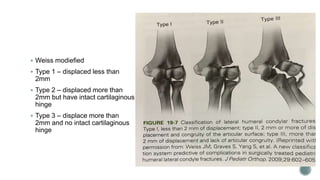

 Weiss modiefied

 Type 1 – displaced less than

2mm

 Type 2 – displaced more than

2mm but have intact cartilaginous

hinge

 Type 3 – displace more than

2mm and no intact cartilaginous